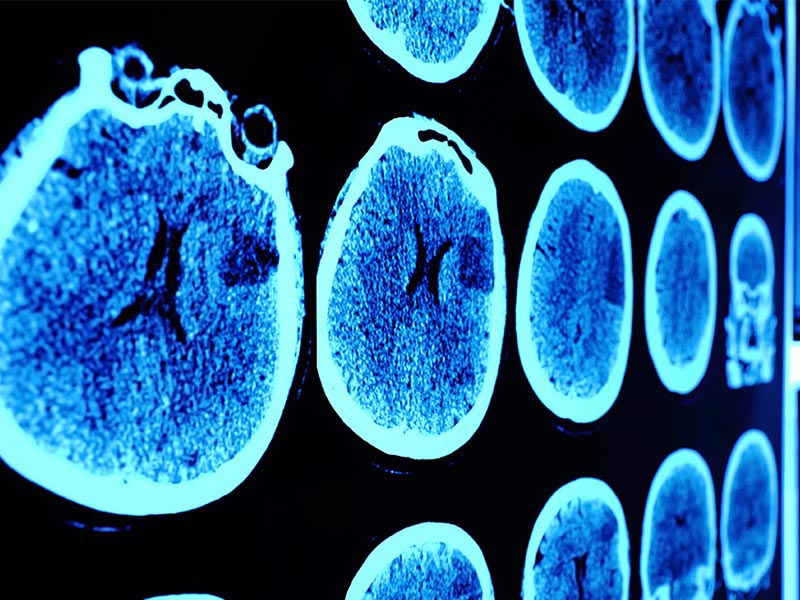

تشخيص سرطان المخ

يتضمن تشخيص سرطان الدماغ إجراء فحص بدني وتاريخ واختبارات التصوير:

• التصوير المقطعي المحوسب: يستخدم الأشعة السينية لإنشاء صور مقطعية للدماغ.

• التصوير بالرنين المغناطيسي: يستخدم المجالات المغناطيسية والموجات الراديوية لإنشاء صور مفصلة للغاية للدماغ والحبل الشوكي.